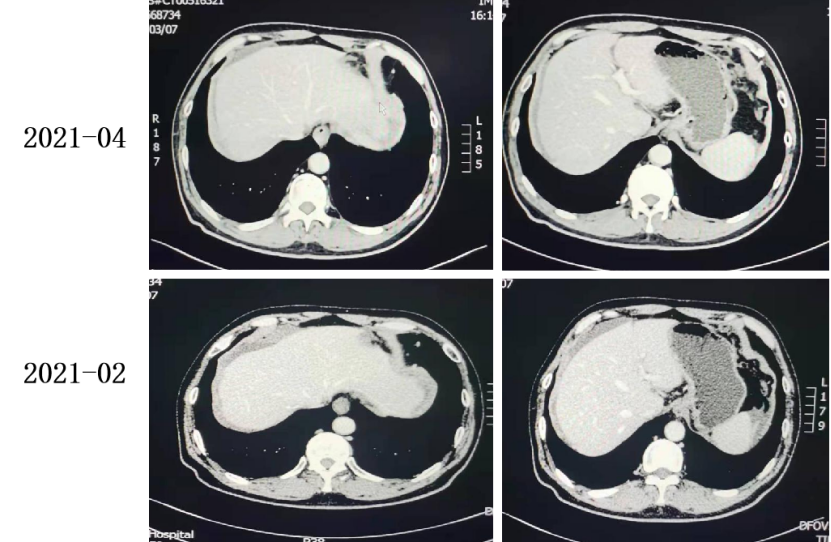

2021-02-24至2021-04-29 2周期 TAS-102+贝伐珠单抗。

2021-04至2021-05 TAS-102+贝伐珠单抗。

复查CT:腹膜增厚,提示腹膜转移,较前变化不大。

2021-06至今 TAS-102+贝伐珠单抗。